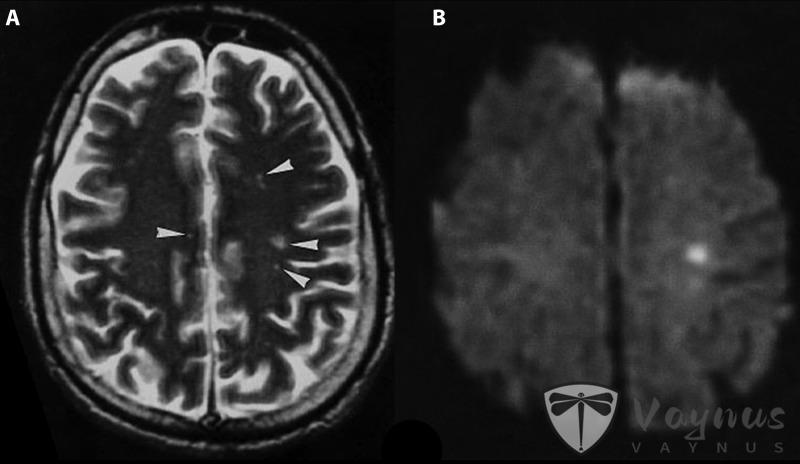

尼帕病毒感染后脑炎的核磁共振图像(图源:参考资料 1)

人类感染包括无症状感染,(轻微或严重的)急性呼吸道感染和致命性脑炎。受感染者最初会出现发烧、头痛、肌痛(肌肉疼痛)、呕吐和喉咙痛等症状。随后可能出现头晕、嗜睡、意识混乱和表明急性脑炎的神经系统体征。有些人还可能出现非典型肺炎和严重呼吸系统问题,包括急性呼吸窘迫。严重病例会发生脑炎和癫痫,进而在24至48小时内陷入昏迷状态。

大多数急性脑炎幸存者可以完全康复,但曾有关于幸存者罹患长期神经系统疾病的报告。大约20%的患者留下神经系统后遗症,如癫痫症和人格改变等。少数人康复后复发或罹患迟发性脑炎。